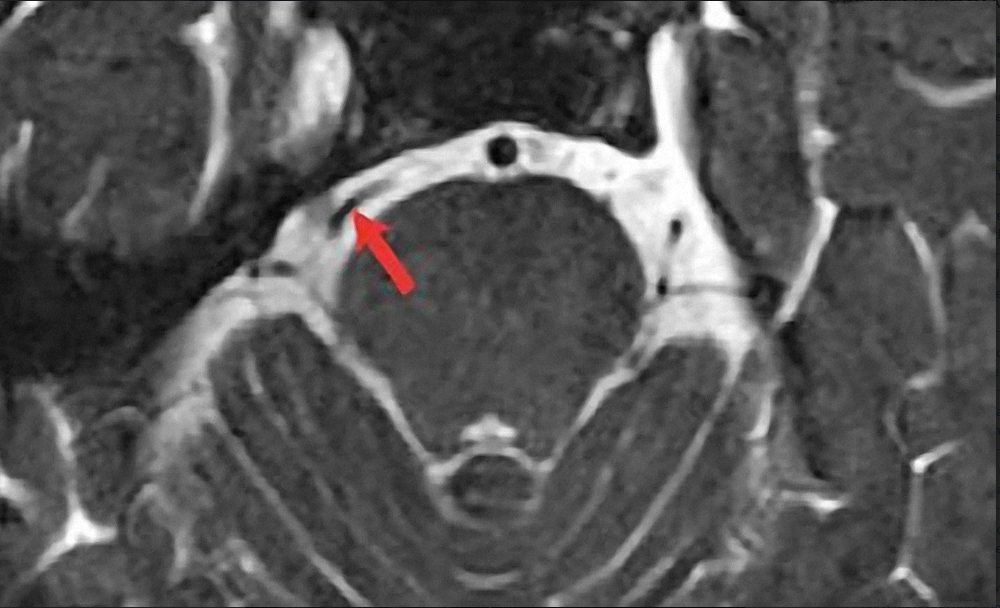

Đây là những chẩn đoán hình ảnh có thể tái tạo ra hình ảnh não và các dây thần kinh trong não vùng hố sau (chuỗi xung CISS 3D) của bạn để xem mạch máu có đè vào dây V hay không?

Hình CHT não chuỗi xung CISS 3D thấy mạch máu đè vào dây V